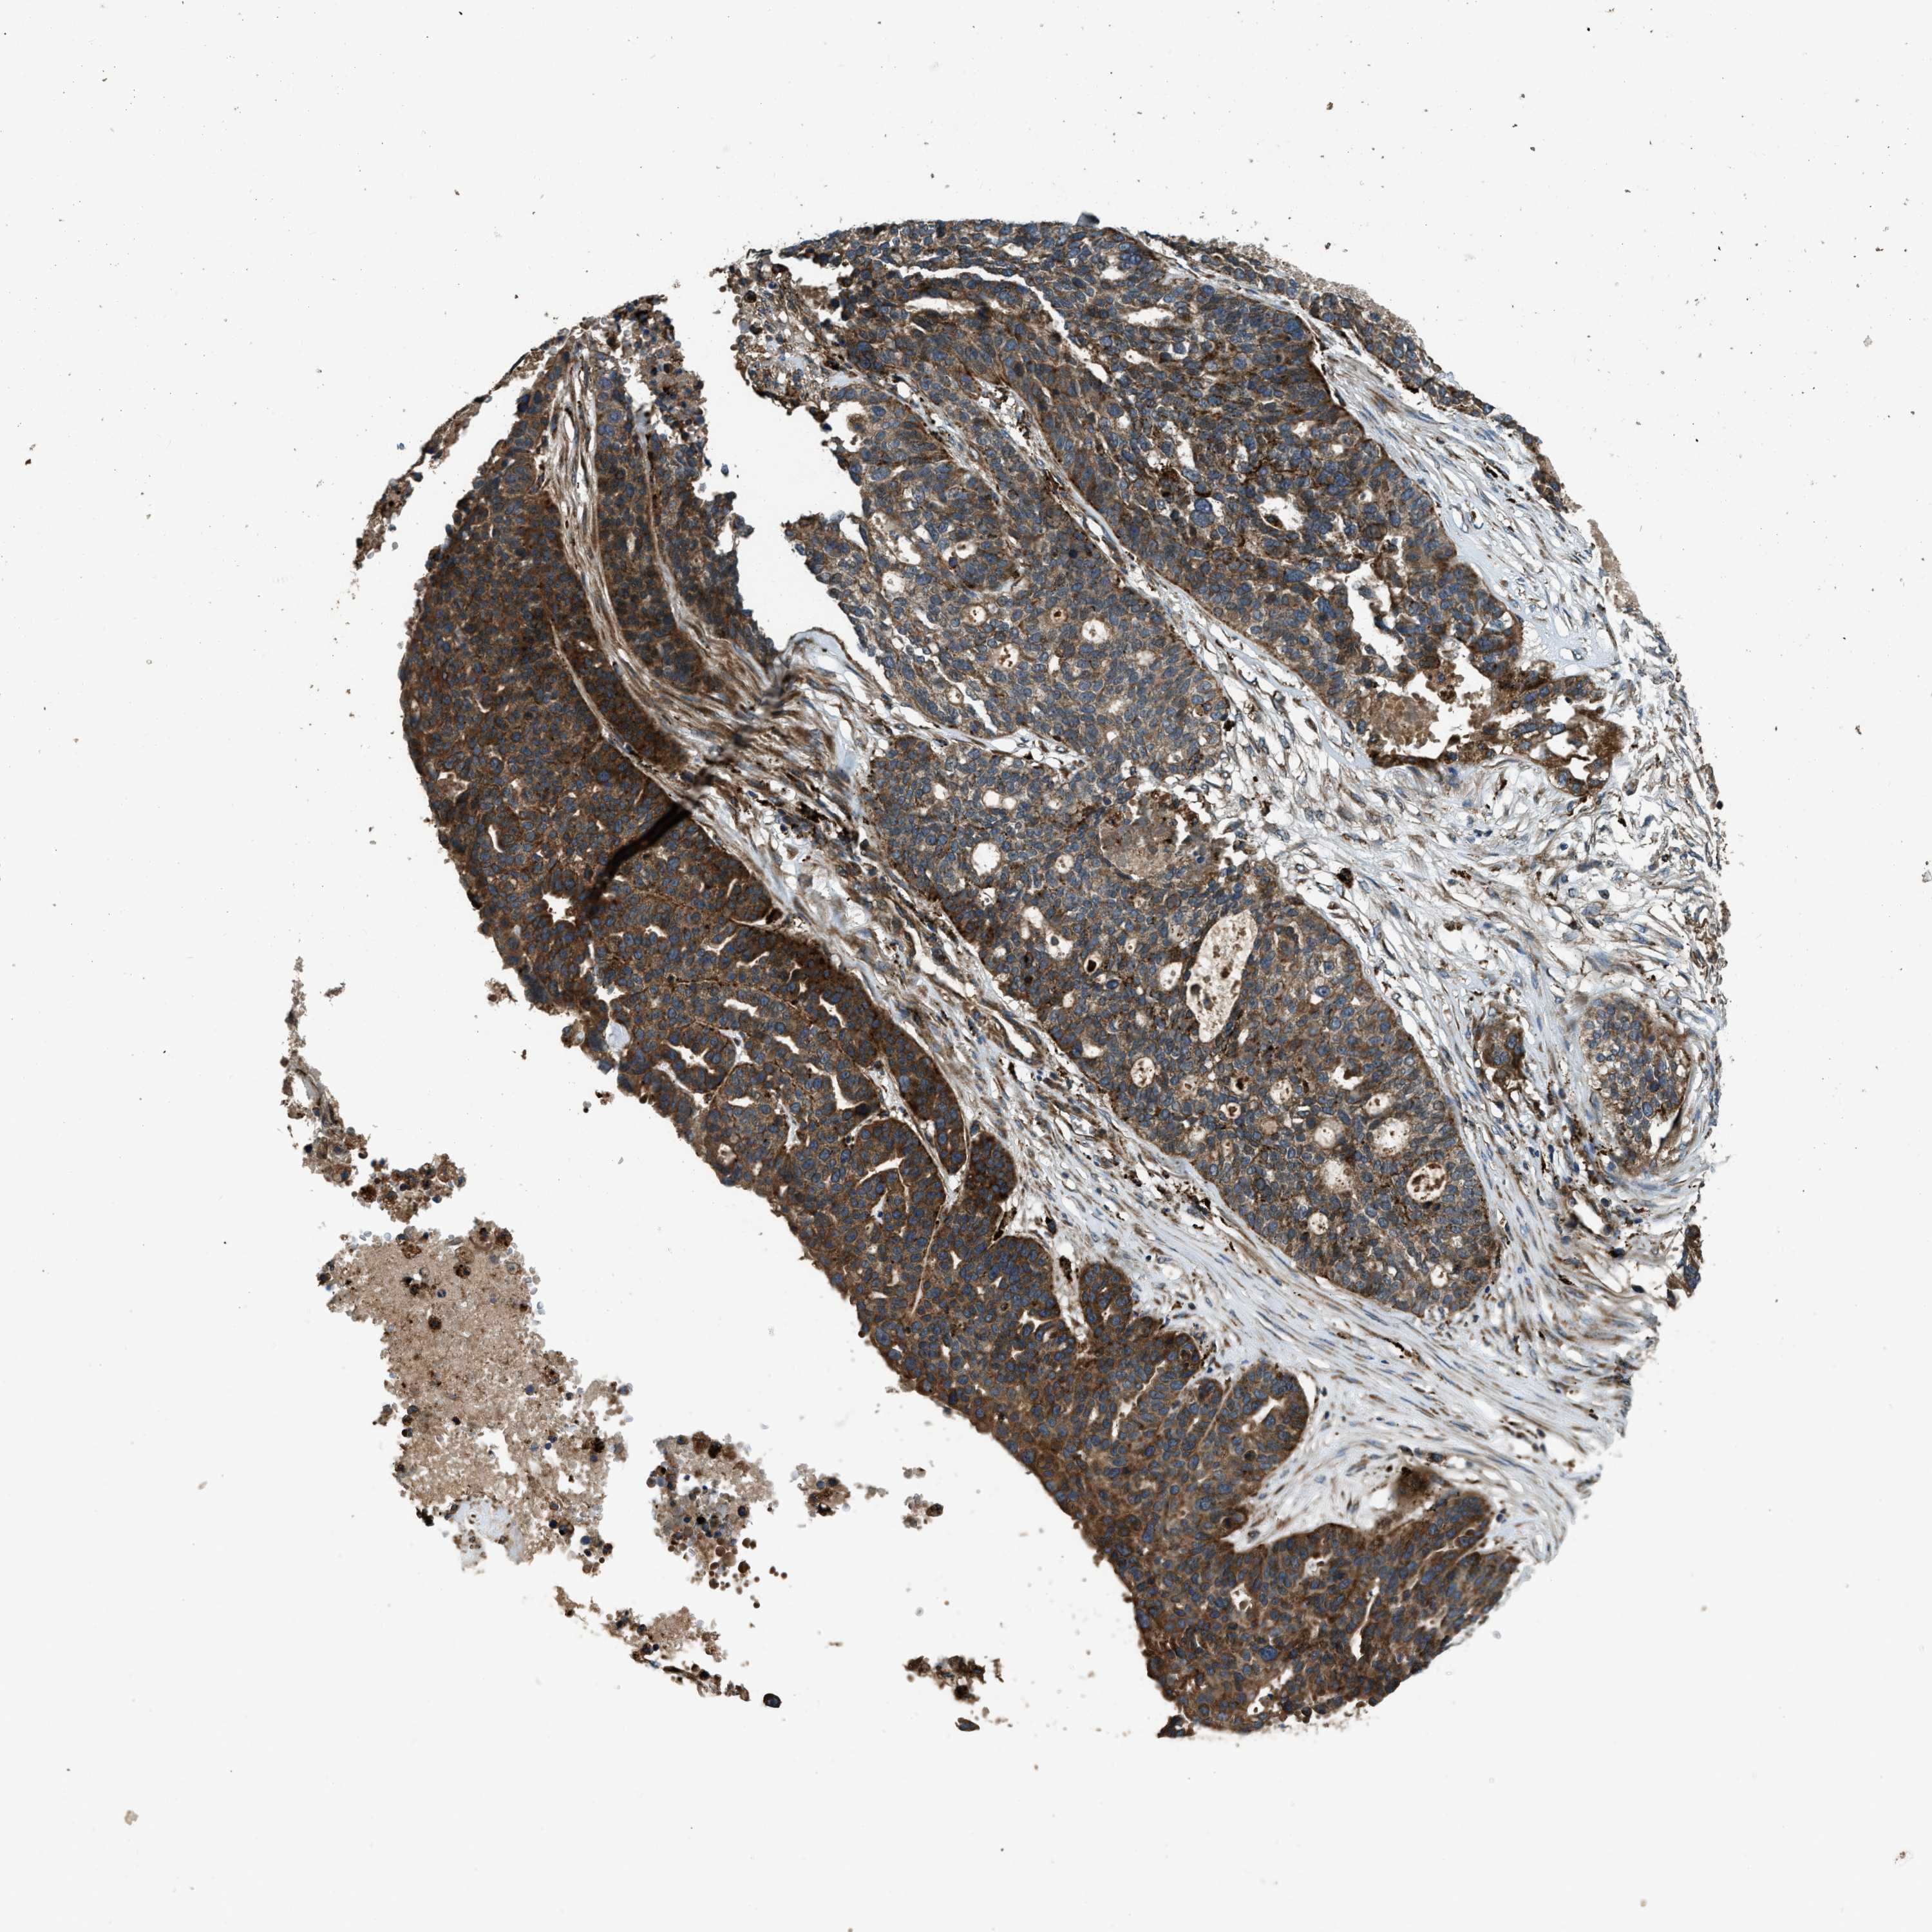

OVARIAN CANCER - Protein expressioni

A mouse-over function shows sample information and annotation data. Click on an image to view it in a full screen mode. Samples can be filtered based on level of antibody staining by selecting one or several of the following categories: high, medium, low and not detected. The assay and annotation is described here.

Note that samples used for immunohistochemistry by the Human Protein Atlas do not correspond to samples in the TCGA dataset.

Antibody stainingi

Antibody staining in the annotated cell types in the current human tissue is reported as not detected, low, medium, or high, based on conventional immunohistochemistry profiling in selected tissues. This score is based on the combination of the staining intensity and fraction of stained cells.

Each image is clickable and will lead to virtual microscopy that enables deeper exploration of all samples and also displays staining intensity scores, fraction scores and subcellular localization as well as patient and tissue information for each sample.

Antibody HPA025226

Antibody CAB019296

Staining

High

Medium

Low

Not detected

Intensity

Strong

Moderate

Weak

Negative

Quantity

>75%

75%-25%

<25%

None

Location

Nuclear

Cytoplasmic/membranous

Cytoplasmic/membranous,nuclear

Cystadenocarcinoma, serous, NOS

Carcinoma, endometroid

Cystadenocarcinoma, mucinous, NOS

Carcinoma, NOS